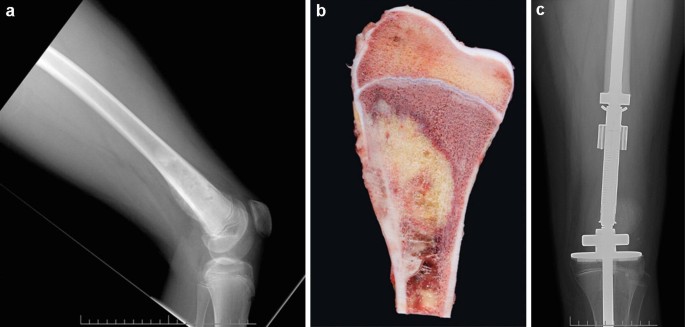

- Imaging tests such as X-ray, MRI, CT scan, or bone scan

- Biopsy to confirm the type and stage of cancer

Surgery

- Removes the tumor and surrounding healthy tissue

- Limb-sparing surgery is common in many cases

- Amputation may be needed in severe or advanced cases